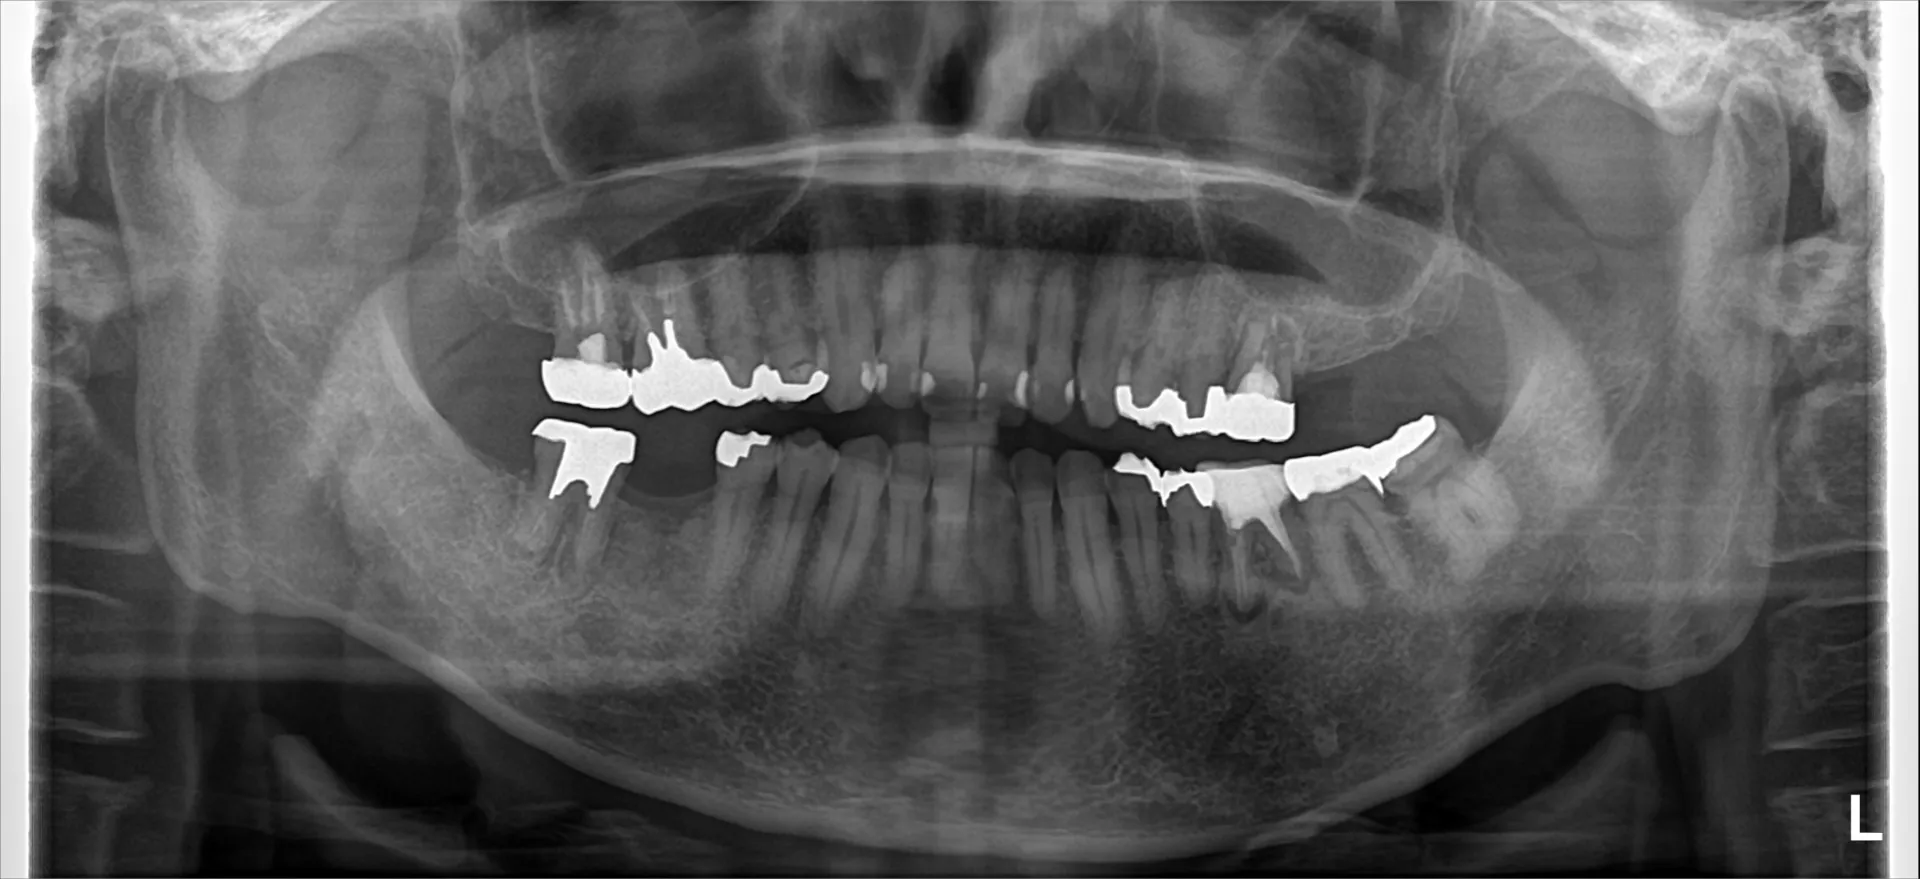

今回は抜歯になってしまった歯からインプラント治療完了までの流れについてご紹介いたします。